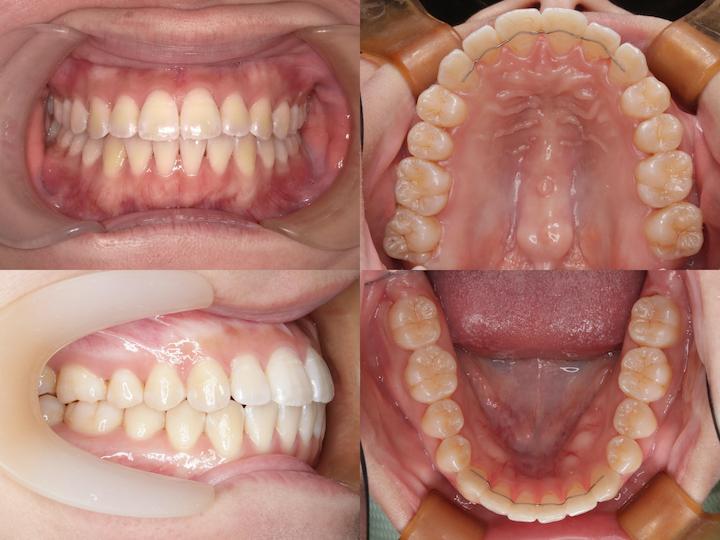

Before

After

治療期間: 1年5ヶ月

上下顎4番を抜歯して、アンカースクリューで大臼歯を固定し、前歯を後方に移動しました。

初診時年齢24歳10ヶ月の患者様です。

口の閉じ辛さと歯の重なりを主訴にご来院されました。

上下左右4番を抜歯してアンカースクリューで上顎6番を固定して前歯を後方に牽引しました。

さらに下顎骨が後方位だったため、上顎大臼歯を圧下(上方向に移動)して下顎骨の前上方への回転を促しました。

本症例は治療期間が1年5ヶ月と比較的短く、前歯の移動量が大きいことから後戻りリスクが高くなります。

フィックス型リテーナーで前歯を固定して、その上から1.0mmのマウスピースで後戻りを防止しています。